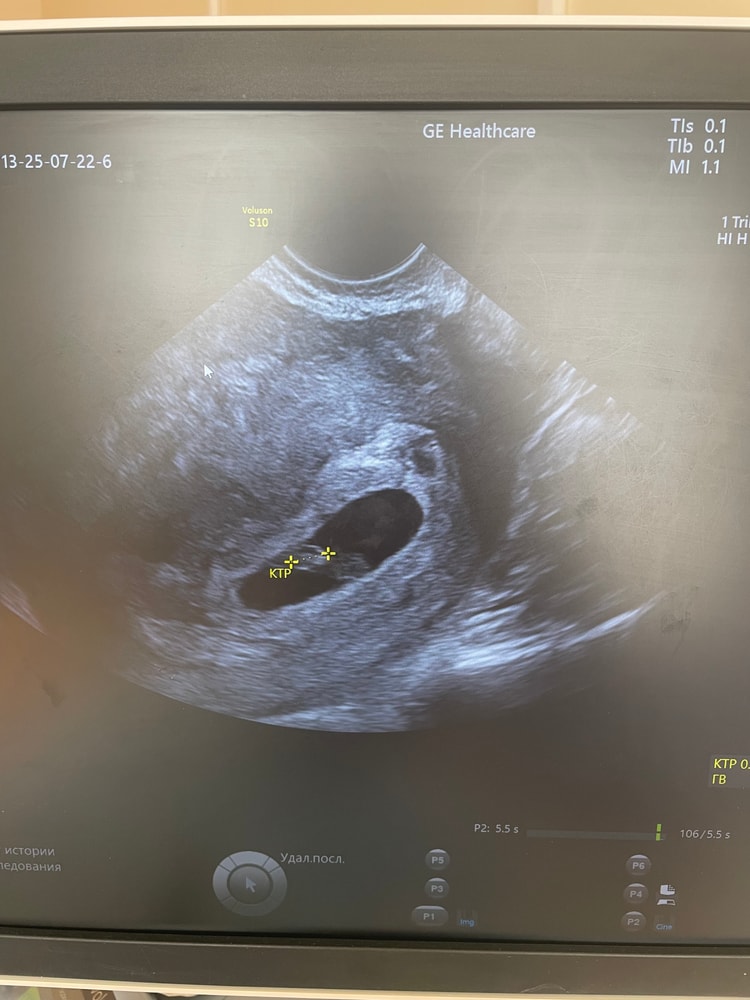

Катя в Зачатие 5 месяцев УЗИ 6,4 УЗИ Сходила сегодня на узи , послушала сердцебиение 124 удара , боже какое это счастье , креветочка уже 5 мм, сказали все соответствует сроку ❤️ пусть и дальше все будет благополучно 🙏 Посмотрите еще 20 записей на эту тему Лучший ответ J Поздравляю вас ♥️🫶🏽 23.07.2025 Ответить Катя J, спасибо 🥰 24.07.2025 Ответить Отменить Ответить Функциональная киста? После ЗБ При каком хгч видно плодное яйцо? Чаты Беременных Выберите чат: Январята-2026 Февралята-2026 Мартята-2026 Апрелята-2026 Майчата-2026 Июнята-2026 Июлята-2026 Августята-2026